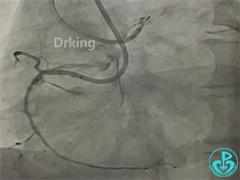

左冠造影:

导丝怎么扩收藏:器械难以通过的CTO病变之技术图谱_https://www.jmylbn.com_新闻资讯_第2张